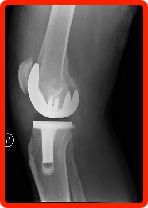

Total Joint Replacement replaces your diseased joint and eliminates the damaged bearing surfaces causing the pain. The implants offer renewed stability, eliminating pain, and providing improved motion with minimum wear and tear. This provides pain-free mobility with a much higher quality of life for the patient. These replacements are most common with knees, hips, and shoulders. In knees, for example, there are other alternatives. The Unicompartmental Partial Knee Replacement involves putting an implant on just one side of the knee. Again, like in joint resurfacing, the doctor is able to eliminate the diseased portion of the knee and leave the healthy portion. By retaining undamaged parts of the knee, the joint may bend better and function more naturally. There are also Unicompartmental Personalized Partial Knee Resurfacing Implants, Bicompartmental Partial Knee Replacement, and Bicompartmental Personalized Partial Knee Resurfacing Implants. |